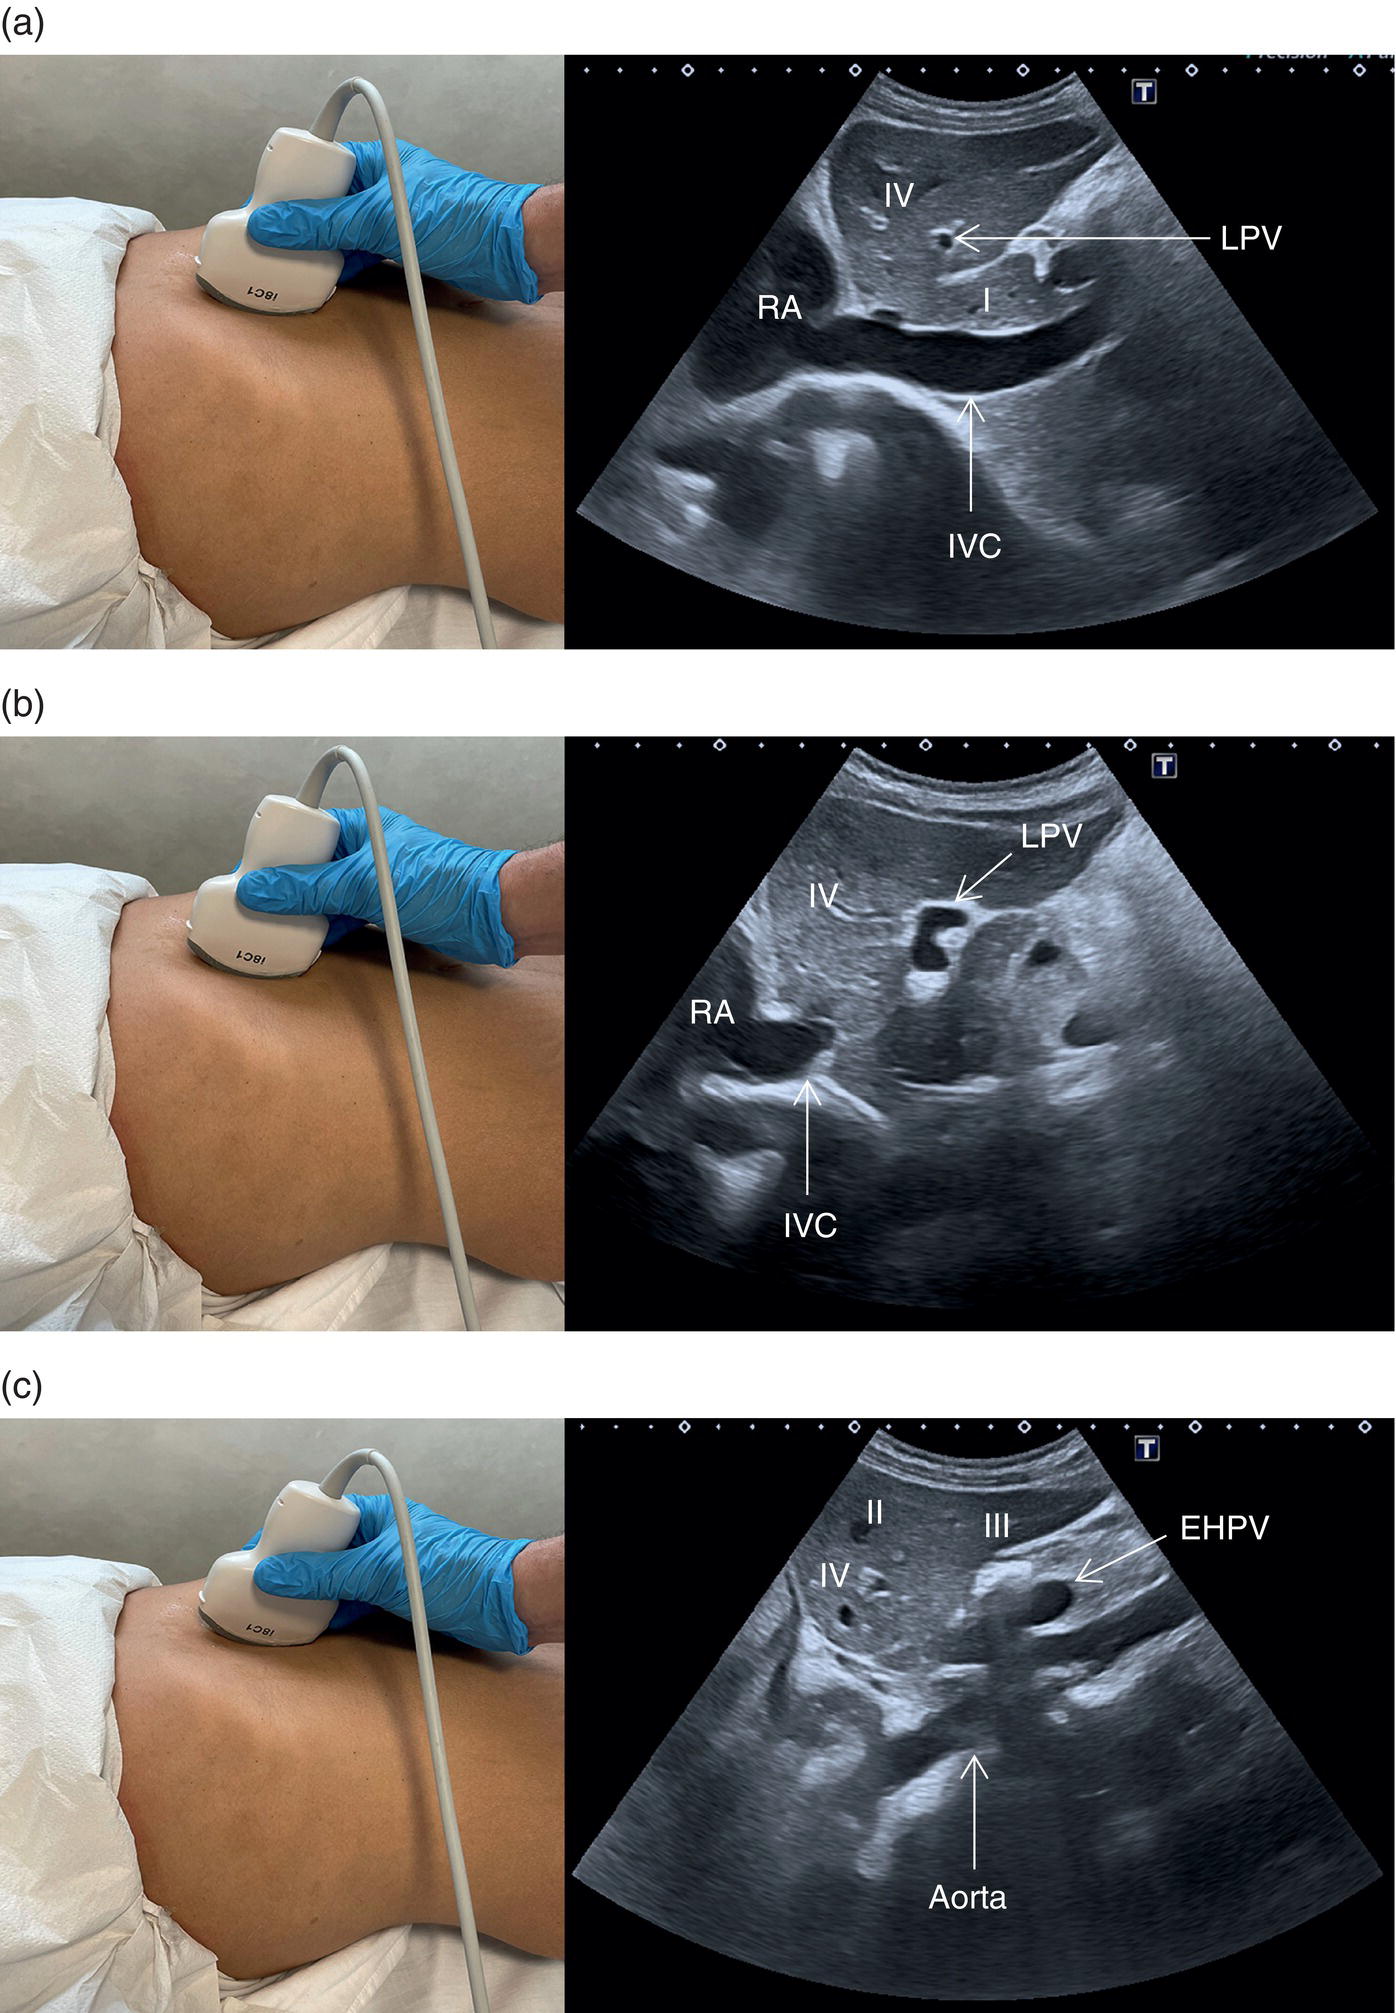

The PV is formed by the confluence of the superior mesenteric vein and the splenic vein, draining the blood of the whole digestive system and spleen (Figure 3.11). Under physiological conditions the portal venous system delivers 75% of the total hepatic inflow, whereas the hepatic artery (HA) is responsible for the remaining 25%. It is important to keep in mind the physiology and pathophysiology of the hepatic blood inflow, since during the progression of liver disease, especially when cirrhosis and portal hypertension develop, the portal venous inflow is reduced while the arterial hepatic inflow is increased (See Chapter 8). The PV can be recognised on ultrasound as a tubular structure with a variable normal calibre of approximately 8–12.5 mm, with thick echogenic walls that enters the liver together with the HA at the level of the hepatic hilum. It is followed by the HA and the biliary system in its whole intrahepatic course and for a short portion in its extrahepatic tract at the level of the porta hepatis, where it is contained within the hepatoduodenal ligament. Upon entering the liver, the PV and HA divide into the left and right branches, with further divisions providing the blood supply to each of the eight main liver segments (Figure 3.12). At the periphery of the liver lobules the arterial and venous blood mix and enter the sinusoids, terminating finally in the central veins that converge to form the right (RHV), middle (MHV), and left hepatic veins (LHV) that finally drain into the IVC (Figure 3.13). It is of note that the caudate lobe is drained independently by a main or multiple small pericaval veins. Its independent venous drainage system is the reason why the caudate lobe typically hypertrophies in advanced chronic liver disease. In Budd–Chiari syndrome, this compensatory mechanism is even more pronounced, since while the main three hepatic veins are obstructed, the pericaval ones often remain patent, leading to an abnormally hypertrophied caudate lobe (See Chapter 11).

Based on the divisions of the portal and hepatic veins, the liver may be divided into eight segments, as first suggested by the French surgeon Claude Couinaud in 1957 (Figure 3.14) [4]. This classification relies on the fact that each of these segments has its own individual blood supply and might be resected without jeopardising the viability of other segments. In this classification, the liver segments II and III are situated to the left of the LHV and falciform ligament, and the left branch of the PV (LPV) divides them into segment II (above the PV) and segment III (below the LPV). Segment IV is situated between the LHV and the MHV and the LPV divides them into segment IVA (above the LPV) and segment IVB (below the LPV). Segments V and VIII are located between the MHV and RHV, whereas segments VI and VII represent most lateral segments situated to the right of the RHV. The right branch of the RPV divides segment V (caudal) from VIII (cranial) and segment VI (caudal) from VII (cranial) (Figure 3.15). On the dorsal, central part of the liver, between the IVC and the venous ligament, lies the caudate lobe that corresponds to segment I (Figures 3.6 and 3.12c).

Start by scanning in the longitudinal scan (LS) plane within the epigastrium, showing segments I and II of the liver, the aorta, and the IVC. Ensure that you sweep from right to left of these liver segments to assess for any focal lesions, contour abnormalities, or biliary tree dilatation. When sweeping left (towards the right side of the patient), the IVC will be more clearly visible, with the caudate lobe well defined between the IVC and the ligamentum venosum (Figure 3.21a); when sweeping right (towards the left side of the patient) the aorta will appear running posteriorly to the left lobe (Figure 3.21b) (see Videos 3.1a and b). Of note are the possibility of accessory lobes (normal anatomical variants), particularly of segment II, which can extend to the left upper quadrant and around the spleen (Figure 3.17). ![]()